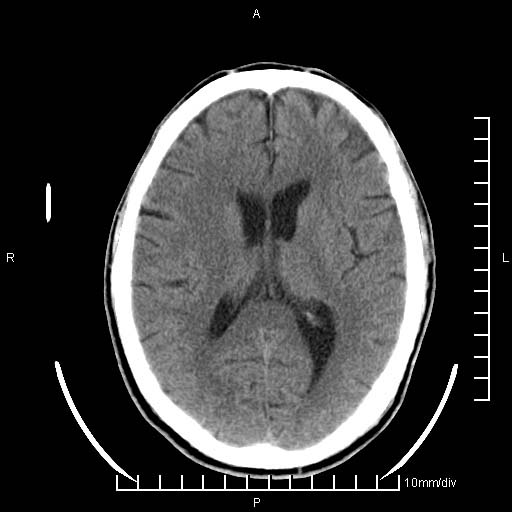

临床以双下肢浮肿,疼痛收治,无明显神经系统症状,既往无梗塞,出血病史。左颞叶见低密度灶,考虑什么?

考虑左侧颞叶脑软化灶。

无强化 无占位 软化灶吧

无强化、 无占位、局部脑沟增宽, 软化灶吧。